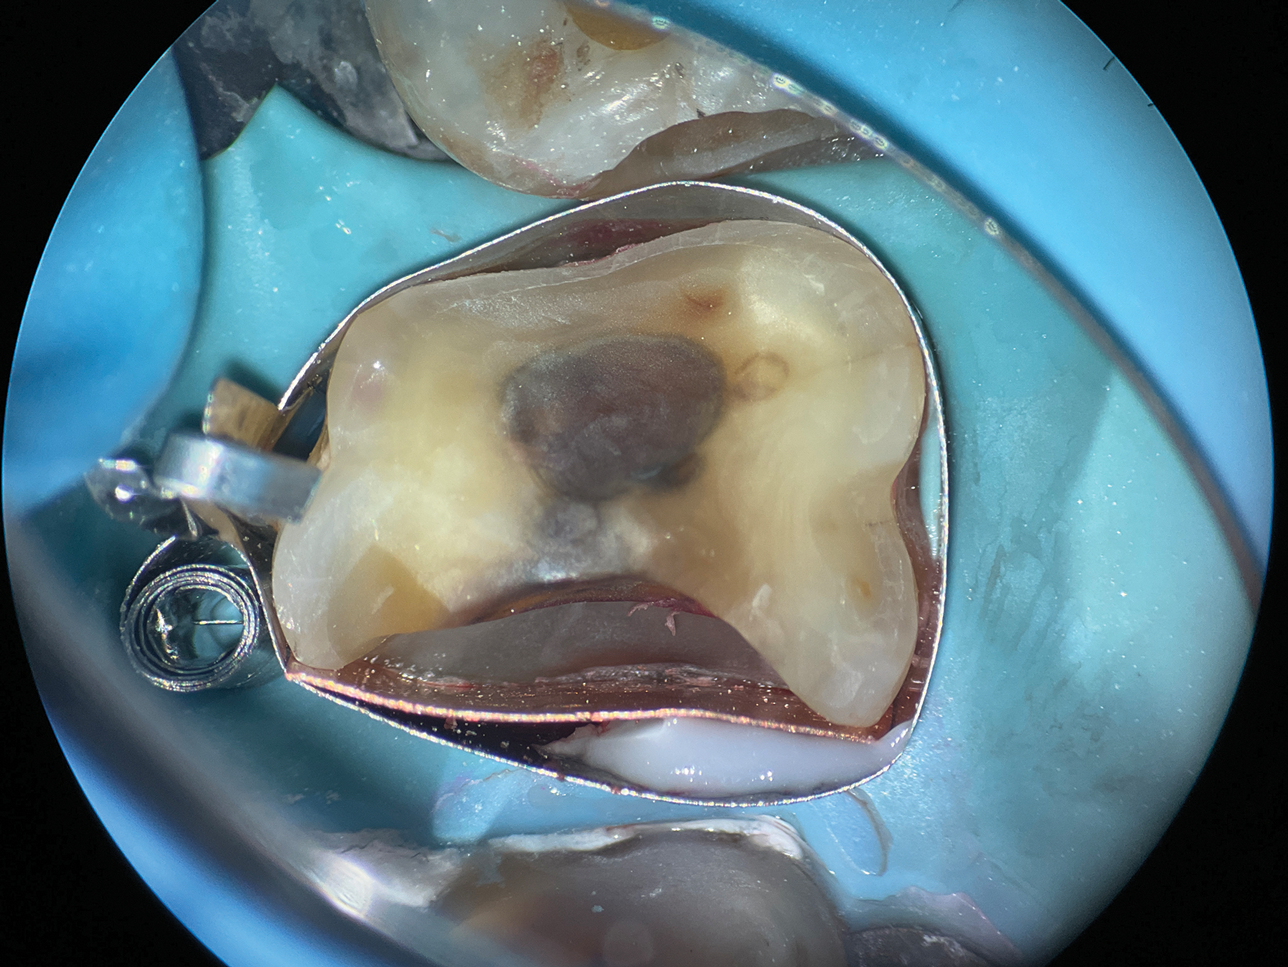

The root surfaces of maxillary molars present unique challenges due to their distinct anatomical concavities. On the mesial surface of the maxillary first molar, a pronounced concavity extends toward the furcation (Figure 7), whereas the distal surface features a broad and shallow depression that extends coronally to the cementoenamel junction. These concavities can pose significant difficulty in restorative procedures, particularly for deep Class II cavities, where their complex morphology complicates the adaptation of a single matrix (Figure 8).

To overcome these challenges, a matrix-in-matrix approach provides a reliable solution (Figure 9). The technique involves placing a circumferential matrix as a base, followed by a precision-shaped copper band with a thickness of 2 to 3 mil. The copper band conforms to the intricate contours of the concavities and serves as an auxiliary support. A liquid dam material is placed between the two matrices for added stability.

(8.) Close-up occlusal view of a maxillary first molar after the removal of deep subgingival caries, where despite rubber dam isolation, infiltration of blood and saliva into the cavity has occurred.

Figure 8

(9.) Close-up occlusal view of the maxillary first molar prepared for a matrix-in-matrix technique with a circumferential matrix supported by a 3-mil copper band inside for proper adaptation to the margin’s concave and convex areas. Note the addition of a liquid dam material placed between the two matrices for added stability.

Figure 9